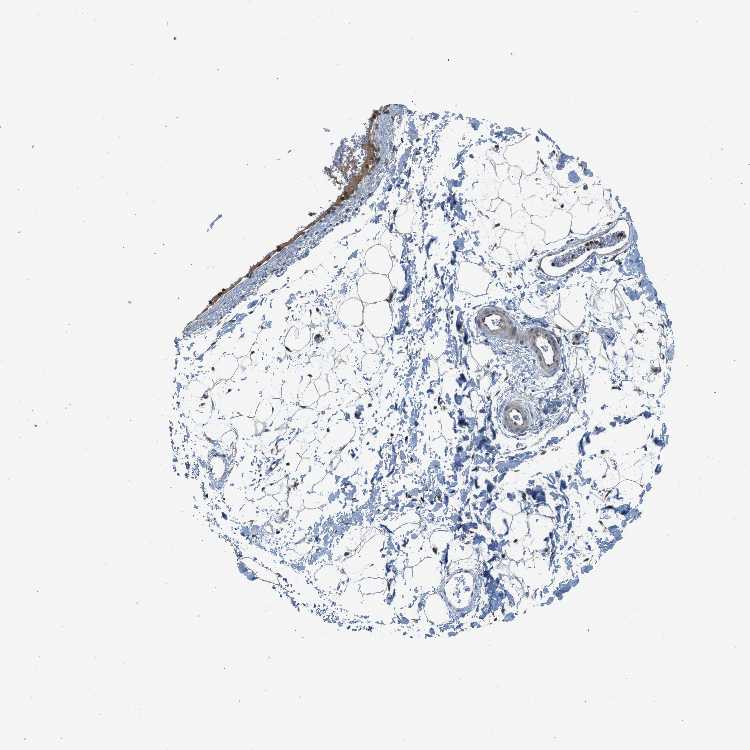

SOFT TISSUE 1 - Antibody stainingi

Antibody staining in the annotated cell types in the current human tissue is reported as not detected, low, medium, or high, based on conventional immunohistochemistry profiling in selected tissues. This score is based on the combination of the staining intensity and fraction of stained cells.

Each image is clickable and will lead to virtual microscopy that enables deeper exploration of all samples and also displays staining intensity scores, fraction scores and subcellular localization as well as patient and tissue information for each sample.

Antibody HPA014657

Chondrocytes High

Fibroblasts Medium

SOFT TISSUE 2 - Antibody stainingi

Peripheral nerve Not detected